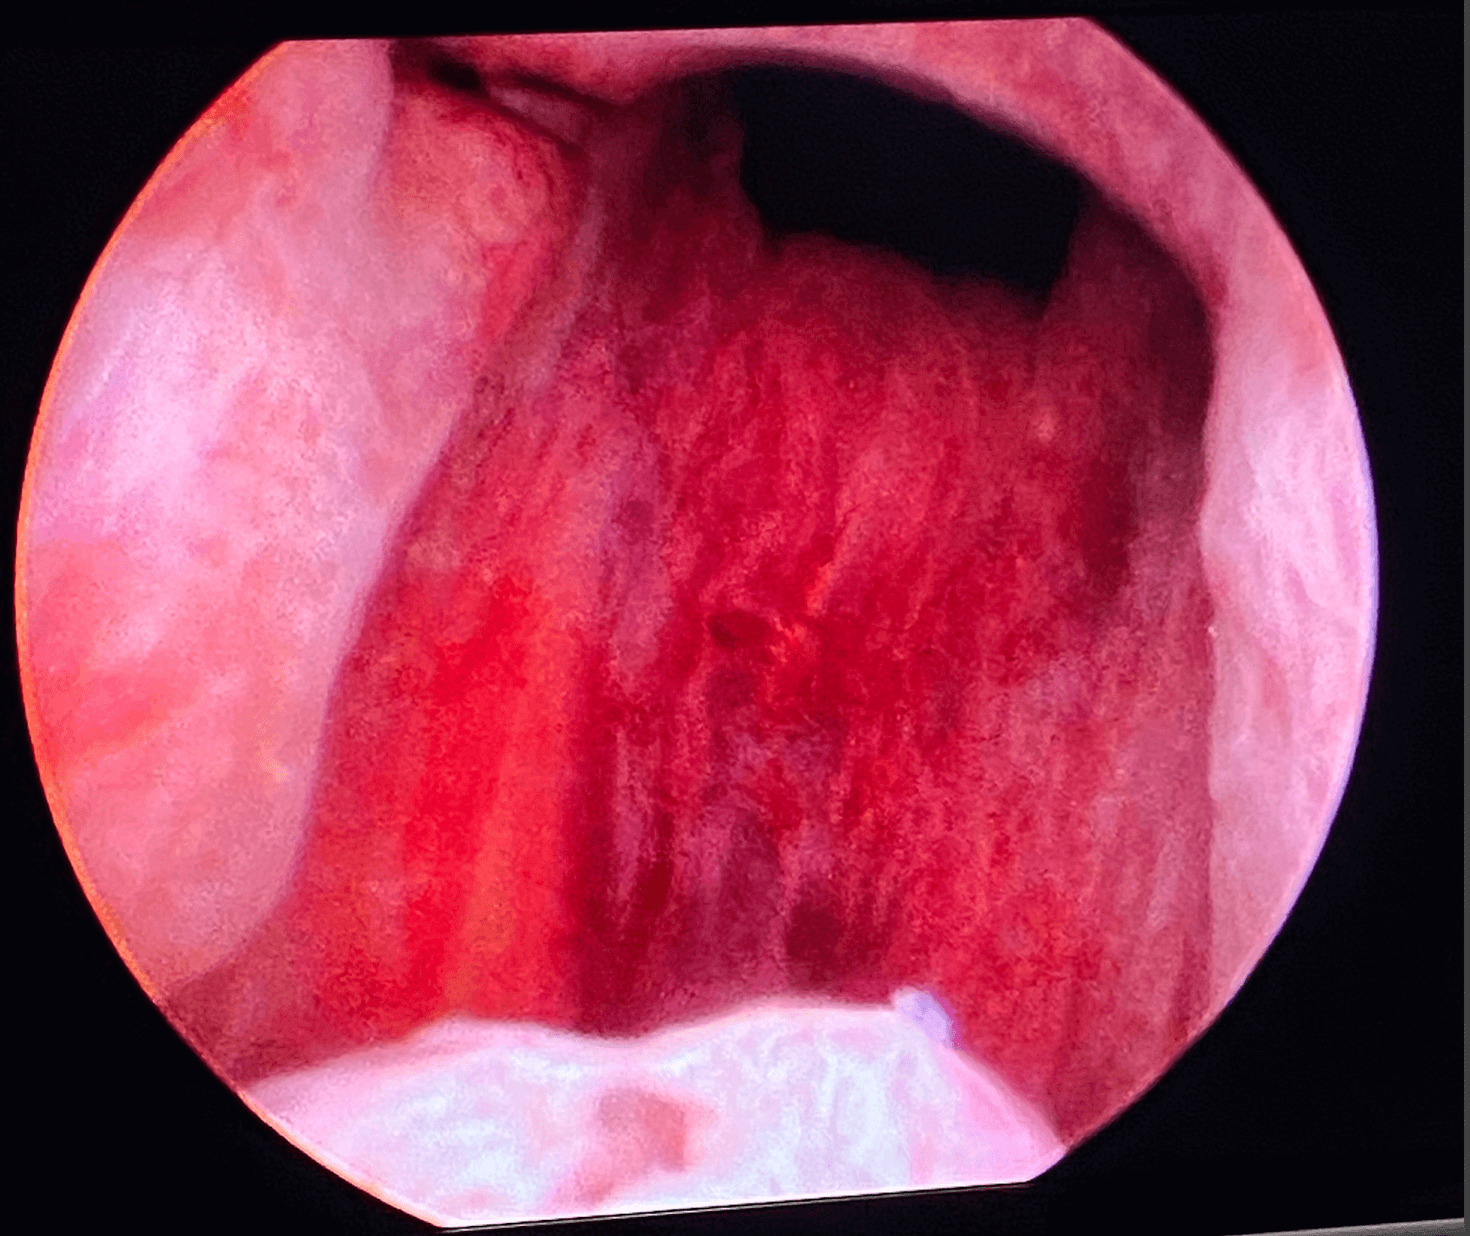

Before & After Pics of UroLift in Atlanta

Procedure

Procedure Details